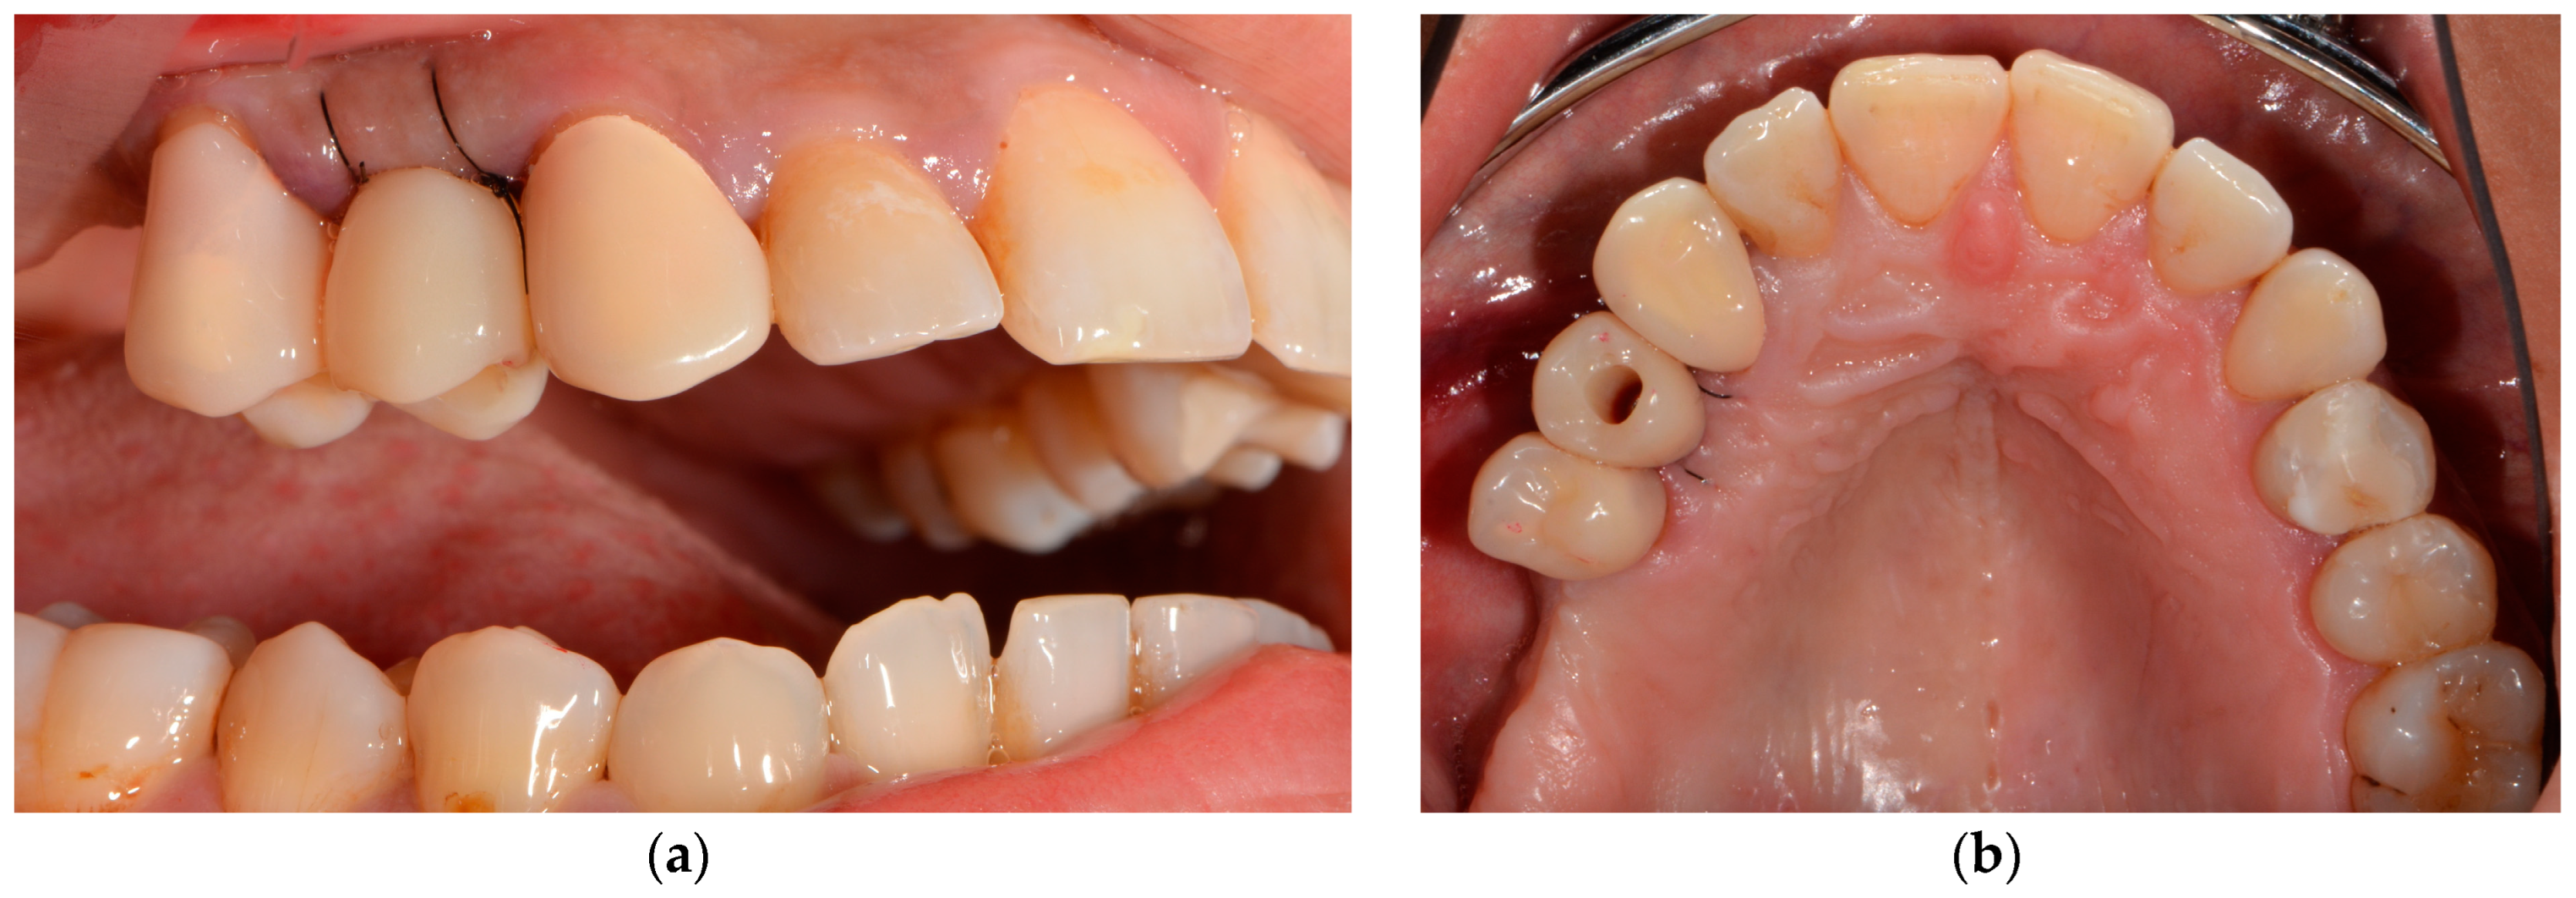

| Restorative | Intraoral scans with a scanbody |

| Chairside, computer-aided design and milling of the provisionalization | |

| Placement of the chairside LTT |